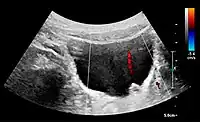

Doppler ultrasonography of the kidney is widely used, and the vessels are easily depicted by the color Doppler technique in order to evaluate perfusion. Applying spectral Doppler to the renal artery and selected interlobular arteries, peak systolic velocities, resistive index, and acceleration curves can be estimated (Figure 4) (e.g., peak systolic velocity of the renal artery above 180 cm/s is a predictor of renal artery stenosis of more than 60%, and a resistive index, which is a calculated from peak systolic and end systolic velocity, above 0.70 is indicative of abnormal renovascular resistance).[1]

Doppler ultrasound (US) of a normal adult kidney with the estimation of the systolic velocity (Vs), the diastolic velocity (Vd), acceleration time (AoAT), systolic acceleration (Ao Accel) and resistive index (RI). Red and blue colors in the color box represent flow towards and away from the transducer, respectively. The specrogram below the B-mode image shows flow velocity (m/s) against time (s) obtained within the range gate. The small flash icons on the spectrogram represent initiation of the flow measurement.[1]